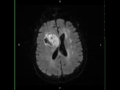

Glioblastoma

68-year-old male with new onset seizures. A centrally hemorrhagic and necrotic lesion is demonstrated within the right frontal lobe and extending into the right striatocapsular region. The lesion effaces the frontal horn and body of the right lateral ventricle with contact and leftward displacement of the septum pellucidum. There are components of the lesion which demonstrate restricted diffusion and heterogeneous contrast enhancement. The differential diagnosis includes glioblastoma, metastatic disease, and CNS lymphoma. The findings are most compatible with a gliobastoma given its solitary nature and lack of increased blood volume on the perfusion maps, not shown. The supratentorial compartment is the most common location for glioblastoma to arise. There are two types, de novo lesions and lesions which degenerate from lower grade astrocytomas. Peak age of occurrence is between 45 and 75 years of age.